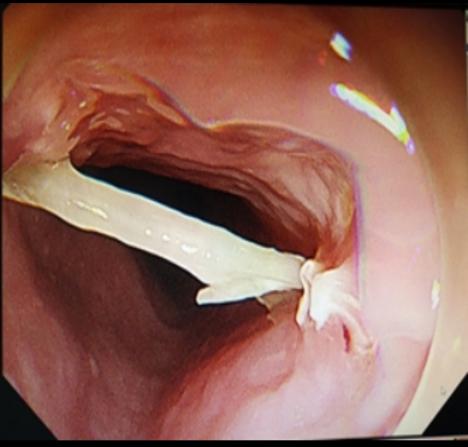

尖銳異物: 魚刺、雞骨頭、假牙等

第二步:立即就醫(yī)內(nèi)鏡中心是首選??捎秒娮游哥R直觀地發(fā)現(xiàn)并取出食道的異物。